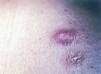

Se realizó biopsia cutánea en el extremo inferior de la placa para estudio histológico (figs. 2-4).

Fig. 2.--Haces de células fusiformes arremolinadas en patrón en rueda de carro.

El estudio histopatológico mostró en la dermis profunda una densa proliferación de células fusiformes con núcleos abombados, levemente pleomórficos. Éstas estaban dispuestas en haces entrelazados con un patrón arremolinado en torno a un eje central constituido fundamentalmente por colágeno y alcanzaban el tejido celular subcutáneo.

La apariencia histopatológica típica del DFSP consiste en una densa proliferación de células fusiformes con núcleo abombado, dispuestas en haces arremolinados en un patrón estoriforme denominado en rueda de carro, alrededor de áreas acelulares centrales de tejido colágeno 4. Desde esta zona parten radialmente fascículos de células neoplásicas que invaden el tejido adiposo subcutáneo desde la dermis profunda, ya sea dejando islotes de adipocitos entre los fragmentos del tumor (patrón en panal de abejas, 30 % de los casos), ya sea en bandas paralelas a la epidermis (patrón en hojaldre, 60 % de los casos). Las células muestran grandes núcleos ligeramente pleomórficos, con escasas figuras mitóticas. En su periferia, el tumor tiende a crecer emitiendo prolongaciones mal delimitadas, lo que explica la dificultad clínica e histológica para determinar sus límites y la elevada tasa de recurrencia tras la extirpación quirúrgica convencional 8. El DFSP muestra positividad para CD34 y negatividad para factor XIIIa y proteína S-100, de gran valor para el diagnóstico diferencial con otros tumores.